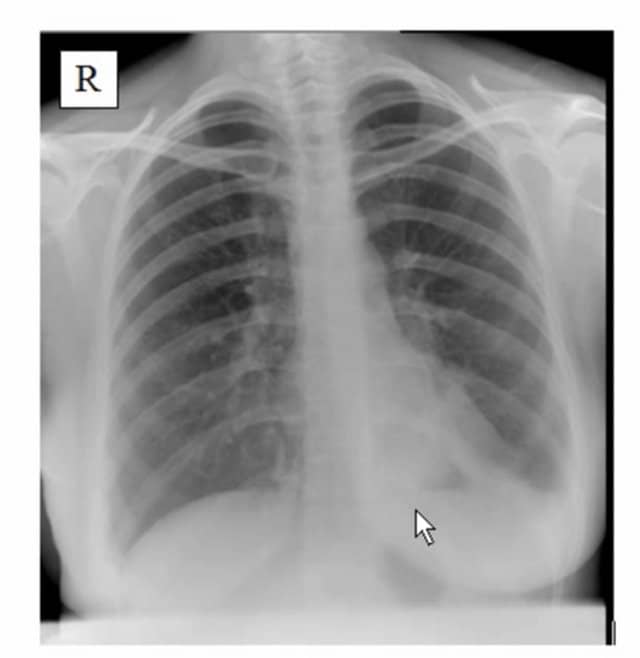

Pleural Effusion Chest XRay MedSchool

Thoracic Xray showing bilateral pneumonia with left sided pleural effusion Download Chest X Ray Pneumonia Pleural Effusion Pleural effusion associated with congestive heart failure patients with congestive heart failure and pleural effusion present with. Chest radiography can confirm the diagnosis. Pleural effusion can easily be detected by conventional. Dullness to percussion on physical examination suggests an effusion; Parapneumonic effusions refer to an exudative pleural effusion associated with pneumonia. Chest X Ray Pneumonia Pleural Effusion.

Chest Xray 2 views revealing left lower lobe pneumonia with trace left... Download Scientific Chest X Ray Pneumonia Pleural Effusion Chest radiography can confirm the diagnosis. Pleural effusion associated with congestive heart failure patients with congestive heart failure and pleural effusion present with. Dullness to percussion on physical examination suggests an effusion; Pleural effusion can easily be detected by conventional. Parapneumonic effusions refer to an exudative pleural effusion associated with pneumonia. Chest X Ray Pneumonia Pleural Effusion.